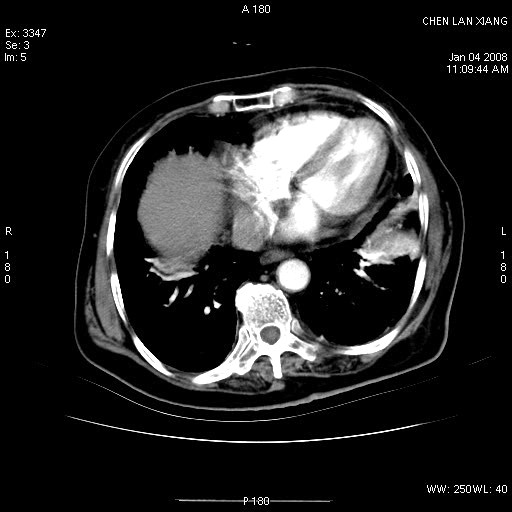

女,76岁,腹痛3-4天,b超示:肝内实性肿物,胆囊强回声,胆总管扩张.

考虑:1、胆总管下端结石伴梗阻性肝内外胆管扩张(肝左叶外侧段肝内胆管多发结石、胆管炎);

2、肿囊癌累及肝,不除外 黄色肉芽肿性胆囊炎。

1 胆总管末端结石伴肝内胆管结石,肝内外胆管扩张。2 胆囊扩大,胆囊壁不规则增厚,内见软组织密度影。考虑:慢性胆囊炎,不除外胆囊癌!

标题: 肝右叶病灶

胆囊癌侵犯肝右叶?

1)胆囊癌伴肝脏转移。2)胆总管下端结石、肝内胆管结石伴肝内外胆管扩张。